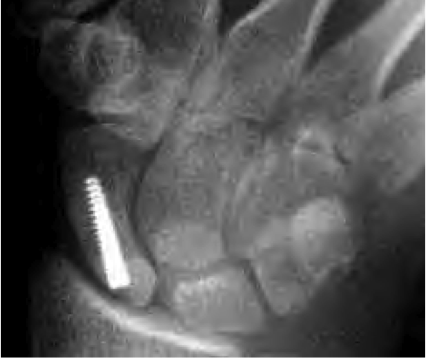

Scaphoid with Acutrak screw

Published November 19, 2013 at 426 × 358 in Scaphoid Fracture